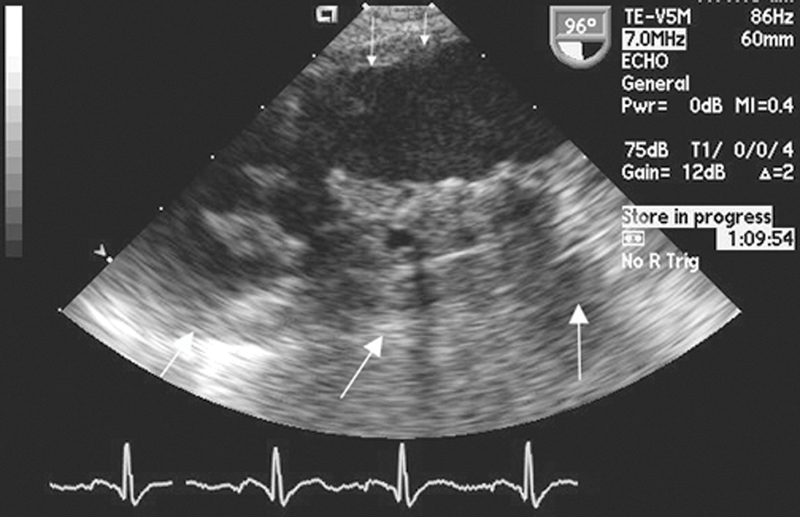

فحوصات تشخيصية لبعض امراض القلب والشرايين التاجية